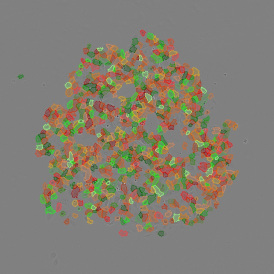

The IF 2 App provides single cell-based co-expression analysis for two IF markers. It segments cells into their nucleus, perinuclear area, and/or cytoplasm. Each segmented cell compartment is measured for up to 20 intensity, statistic, and morphometric parameters that can be displayed in and exported into scattergrams and histograms.

App Category 1